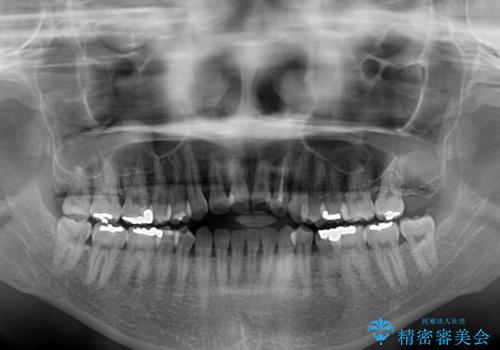

開咬と変色した前歯 インビザライン矯正とオールセラミッククラウン治療

- 前歯の開咬と失活により変色した前歯を気にして来院された患者様です。

開咬の治療は、前歯を閉じるように引っ張り出すよりも、上下臼歯を圧下(骨内にめり込ませる)させることで進める方が長期的に安定した歯列を維持できます。

インビザラインは臼歯の圧下を効果的に行えるため、インビザラインを用いて矯正治療を行うこととしました。

矯正治療が概ね終了した時点で前歯をオールセラミッククラウンにて補綴治療を行い、その後インビザラインにて細かい部分を仕上げていくことしました。